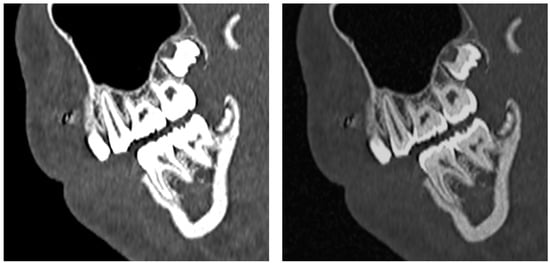

3.5.2. Dental Decay Radiologic Correlations